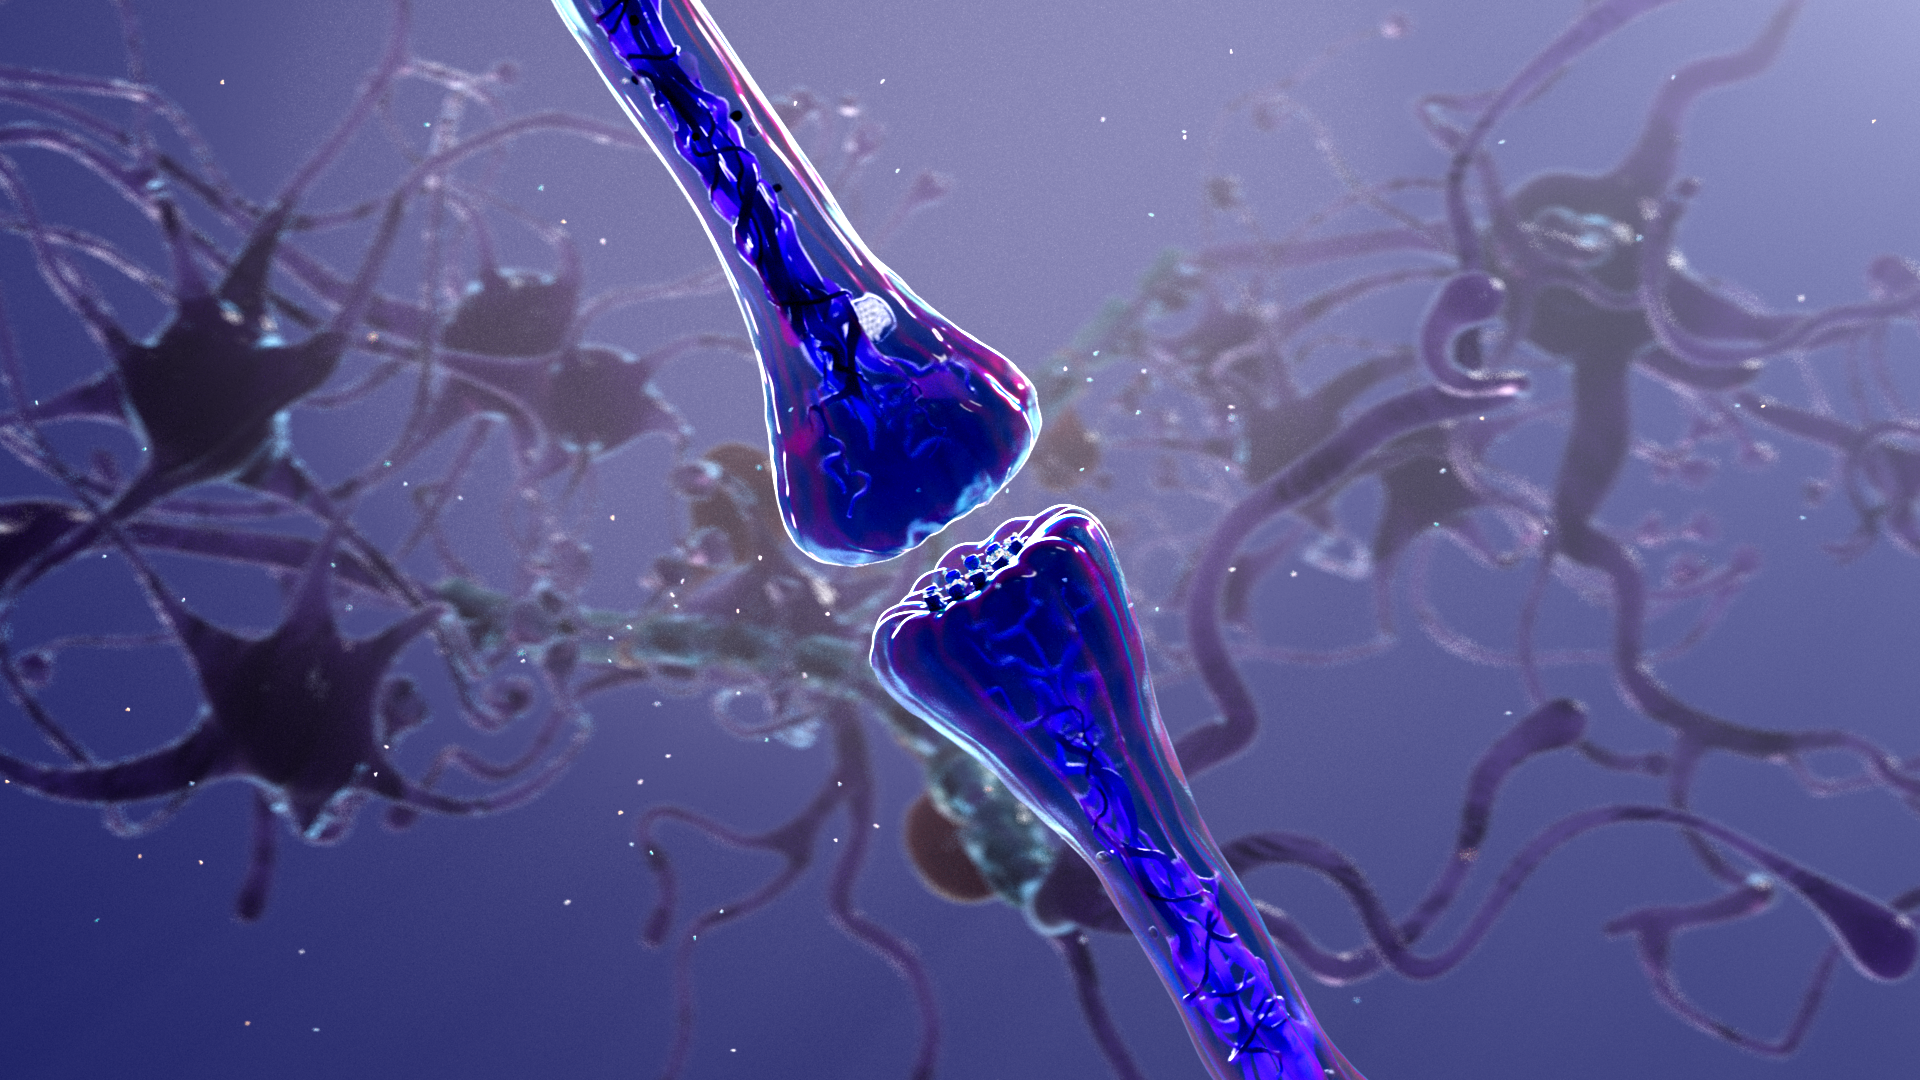

Empyrean Neuroscience is developing first-in-class, neuroactive therapeutics using genetic engineering to improve the lives of patients suffering from debilitating neuropsychiatric and neurologic disorders.

We developed an engaging 3D animation that details the “entourage effect”, a cascade of small molecules inherent to plants and fungi that work in concert to generate positive patient experiences and health benefits.

The animation we produced successfully addresses both patient and provider audiences, and showcases the benefits Empyrean’s platform enables for people suffering from depression and anxiety.